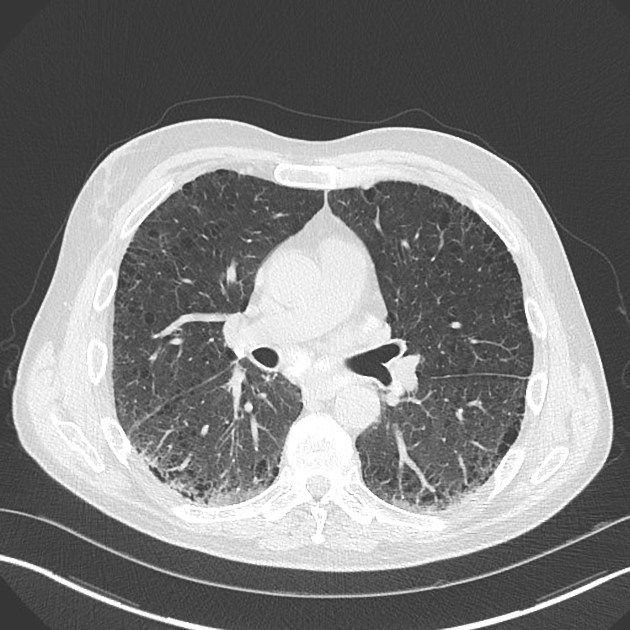

Rheumatoid pneumoconiosis refers to inflammation and scarring of the lungs. It is associated with rheumatoid arthritis and develops in individuals who are exposed to industrial dust. Since rheumatoid arthritis is an autoimmune disease, the excessive stimuli in the form of inorganic dust further intensifies the immune response leading to inflammation of lungs thereby causing rheumatoid pneumoconiosis. Reference: https://medlineplus.gov/ency/article/000137.htm Image via: https://radiopaedia.org/cases/caplan-syndrome